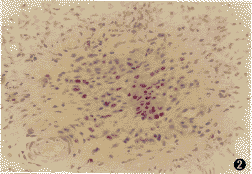

嗜酸粒细胞主要分布于鼻息肉粘膜下固有层。chromotrope 2R染色可特异性地将嗜酸粒细胞的胞浆染成粉红色,可准确辨别嗜酸粒细胞(图1,2),显示组织中嗜酸粒细胞的浸润状况。对照组10例中鼻甲组织中有8例存在嗜酸粒细胞浸润,其中有4例可见散在EG2阳性嗜酸粒细胞。未治组中变应性患者和非变应性患者在EG2阳性细胞密度、chromotrope 2R阳性细胞密度和嗜酸粒细胞活化比例(EG2阳性细胞个数/chromotrope 2R阳性细胞个数)比较差异均未见显著性(P>0.05)。激素治疗组EG2阳性细胞和chromotrope 2R阳性细胞的密度均较未治组减少(图3,4),但差异未达显著性水平(P>0.05)。而激素治疗组嗜酸粒细胞活化比例则明显低于未治组,差异有非常显著性(P<0.01,表1)。

图1 未治组鼻息肉中较多嗜酸细胞浸润。chromotrope2R染色×200

图2 治疗组鼻息肉中嗜酸粒细胞未见显著减少。chromotrope2R×100